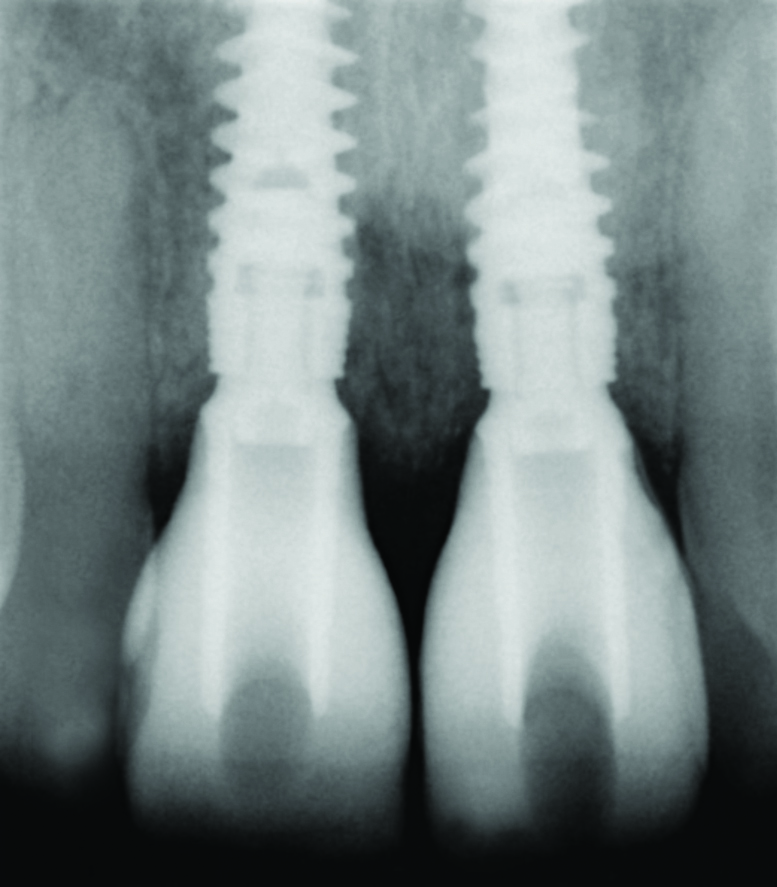

As discussed, new implant designs can influence bone and, therefore, soft-tissue levels and stability along with several other important treatment-planning considerations. Similarly, selection of the correct implant size in an area of treatment also impacts tissue levels around the implant and the adjacent teeth. The use of a small-diameter implant (3 mm) of the platform-switching concept was used in a space of limited mesiodistal dimension. Excellent bone levels were noted around the implant, and importantly, with no adverse effect on marginal bone levels on the adjacent teeth (Figure 25 and Figure 26). If a wider implant diameter had been selected, the periodontium of the adjacent teeth may have been compromised had any remodeling of the bone around the implant occurred.

Fig 25. Preoperative radiograph. Congenitally missing tooth No. 10 presents limited space mesiodistally for a conventional implant diameter.

Figure 25

Fig 26. Postoperative radiograph. A small-diameter implant (3 mm) was ideally placed 3-dimensionally.

Figure 26